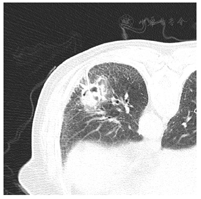

就诊时胸部CT平扫示左肺下叶霉菌球及气囊,肺间质纤维化,双肺多发小结节。结合气管镜肺泡灌洗液NGS及协和医院病理会诊明确诊断慢性肺曲霉病。

患者2019年9月无明显诱因出现咳嗽,咯少量白粘痰,无咯血,无喘憋,无胸痛,未系统诊疗。2019年11月11日自觉咳嗽症状加重,就诊至西安市中医院,查胸部CT示:右肺上叶前段渗出实变病灶,左肺下叶基底段空洞形成。考虑不除外肺结核,转至西安市胸科医院就诊,完善支气管镜检查等相关检查,考虑活动性结核诊断证据不充分,予莫西沙星抗感染及对症治疗,后患者自觉症状略好转。治疗后复查胸部CT示:双肺阴影考虑渗出性病变可能,左肺下叶背段阴影合并曲霉菌感染不除外。后患者未进一步诊治。

2020年5月29日患者咳嗽症状加重,就诊于唐都医院胸外科,查胸部CT示左肺下叶基底段占位性病变,右肺上叶前段、后段及左肺上叶舌段,下叶后基底段,左侧叶间胸膜区散在小结节,双肺间质性改变。于2020年6月1日行经胸腔镜单操作孔左下肺楔形切除术。术后病理:(左肺下叶)肺组织慢性炎伴炎性渗出、坏死,纤维组织增生、炭沫沉积并支气管囊性扩展,局部查见少许真菌,间质内淋巴组织过度增生,部分淋巴细胞及浆细胞增生活跃。诊断"肺真菌球",并予伏立康唑及化痰等对症治疗后出院。出院后患者服用伏立康唑治疗,因转氨酶升高明显,服药1周后停药。后改服伊曲康唑0.2 g 2次/d。患者仍有间断咳嗽,无咯血,伴有左下侧胸部疼痛。2020年9月于唐都医院,查胸部CT提示左残肺术区高密度影较前未见明显变化,于左肺下叶基底段行超声支气管镜探查,给予灌洗及活检检查,病理示:"左肺内基底段"少许支气管黏膜慢性炎及肺组织伴纤维间质组织增生,灌洗液未见结核杆菌、真菌及病毒,NGS检测到副流感嗜血杆菌、流感嗜血杆菌、烟曲霉序列数增加,予伏立康唑0.2 g 1次/12 h联合莫西沙星治疗,出院后规律服用国产伊曲康唑0.2 g 2次/d,仍有咳嗽、胸痛,后患者因服用伊曲康唑出现腹部不适,于2020年11月改服伏立康唑治疗,后规律应用伏立康唑治疗。

经胸腔镜手术术后病理、术后气管镜NGS检测,明确诊断肺曲霉病。结合我院入院时影像,新月征显著,经1年余伏立康唑规范口服抗真菌治疗,于我院就诊时病情稳定,明确为慢性肺曲霉病,表现为简单型曲霉球。